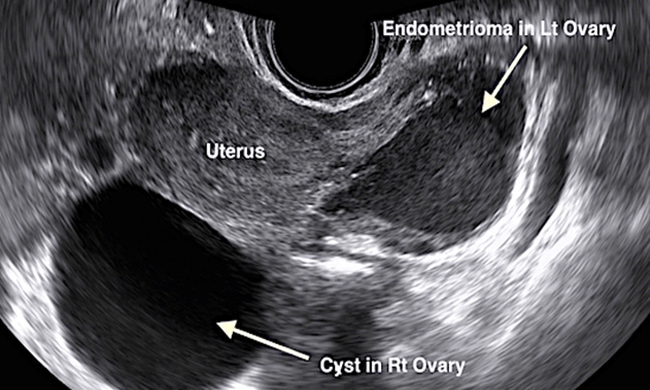

"Blood Cysts" or Endometriomas (or chocolate cysts) are formed by Endometriosis. Endometriosis is a condition where the womb lining is found outside the womb, causing menstruation outside the womb. Endometriosis can form blood cysts inside the ovary leading to painful menstruation and pelvic pain.

"Water Cysts" or Functional ovarian cysts are the most common cysts in the reproductive age. Functional cysts are the result of normal ovulation function. They contain only fluid and usually resolve in a month or two, hence treatment is rarely needed. They are usually less than 5cm although sometimes they can be as large as 8cm.